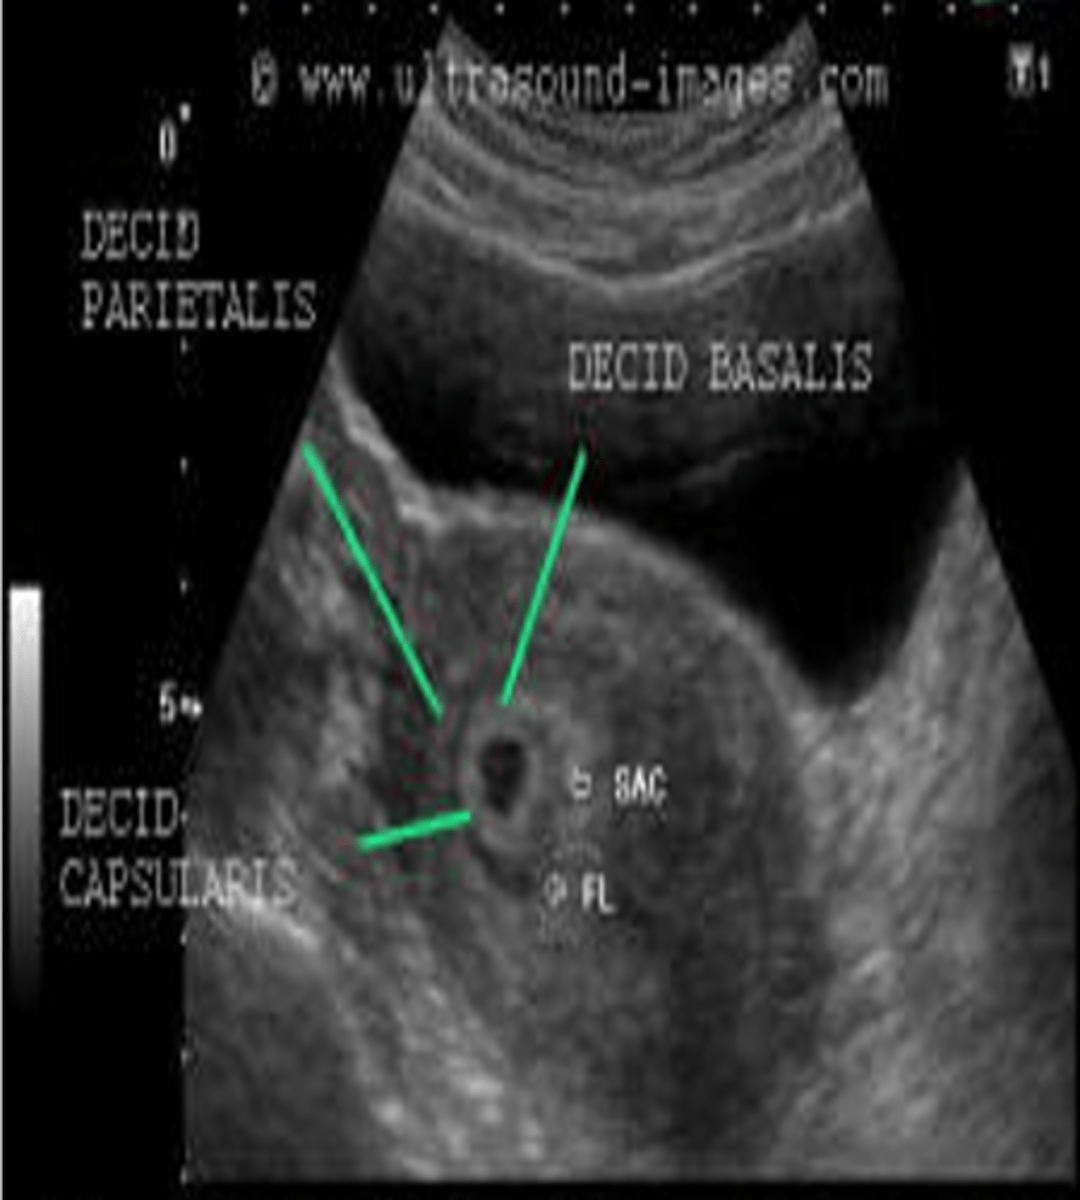

What components can the echogenic ring around the gestational sac be divided into?

decidua basalis

decidua capsularis

double decidual sac sign

The decidua basalis is the ___ on the ___ or burrowing side of the embryo

villi; myometrial (mother's side)

The decidua capsularis is the ___ covering the rest of the ___

villi; developing embryo (baby side)

The double decidual sac sign is an interface between the ___ and the ___

decidua capsularis; endometrium

The double decidual sac sign is a reliable sign of ___

viable gestation

During the 5th week, what is decidua wall thickness?